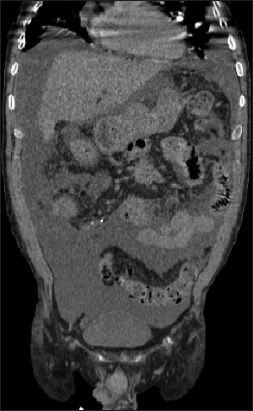

Abstract Image